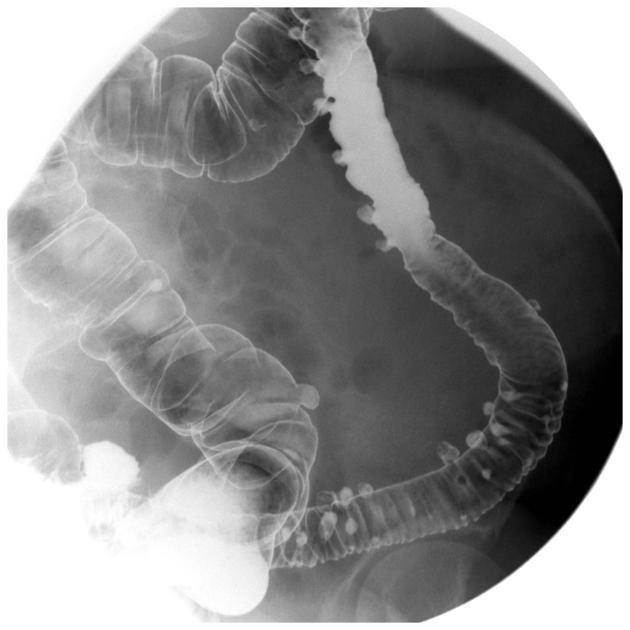

Barium enema showing diverticular disease

Cobblestone appearance of colon

characteristic of Crohns

Kantours string sign